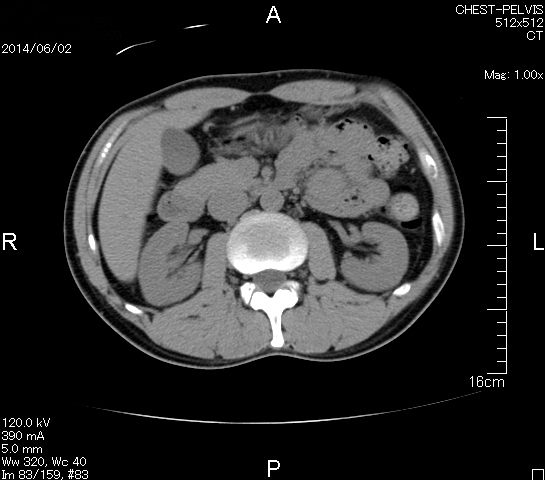

検査結果

マーカー、CT画像、問題なし!!

今回も血液検査結果は正常値のパレード!